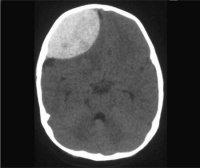

Диагностируется субдуральная гематома головного мозга путем неврологического обследования пациента. Для подтверждения первичного диагноза, определения размера гематомы и наличия осложнений, проводится МРТ и КТ.

Субдуральная гематома на КТ.